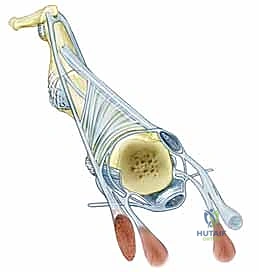

قبل الخوض في التفاصيل التقنية للإجراء الجراحي، من الضروري والمحوري أن نفهم البنية التشريحية المعقدة لمفصل MCP. هذا المفصل هو الرابط الحيوي بين عظام راحة اليد (الأمشاط - Metacarpals) وعظام الأصابع الأولى (السلاميات القريبة - Proximal Phalanges). يُصنف هذا المفصل على أنه مفصل لقمي (Condyloid Joint)، مما يعني أنه يسمح بحركات متعددة في مستويات مختلفة: الثني (Flexion)، البسط (Extension)، الانحراف الزندي (Ulnar Deviation)، الانحراف الكعبري (Radial Deviation)، بالإضافة إلى الحركة الدائرية المحدودة (Circumduction).

- الأربطة الجانبية الكعبرية والزندية (Radial and Ulnar Collateral Ligaments): هذه الأربطة حاسمة للغاية في توفير الاستقرار الجانبي. يتميز رأس العظم المِشطي بتأثير فريد يُعرف بتأثير "الحدبة" (Cam Effect)؛ حيث يزداد قطره وسمكه في المستويين العرضي والسهمي كلما اتجهنا نحو السطح الراحي. هذا التصميم الهندسي الإلهي يعني أن الأربطة الجانبية تكون مشدودة تماماً عند ثني الإصبع (مما يمنع الحركة الجانبية أثناء الإمساك بالأشياء)، وتصبح مرتخية نسبياً عند بسط الإصبع. هذا الارتخاء في وضع البسط هو ما يسمح لنا بفتح أصابعنا وإبعادها عن بعضها (انحراف كعبري وزندي).

- الصفيحة الراحية (Volar Plate): هي بنية قوية جداً، ليفية غضروفية في جزئها البعيد (حيث تتصل بالسلامية)، وغشائية مرنة في جزئها القريب. تعمل هذه الصفيحة كحاجز ميكانيكي حاسم، يحد من فرط بسط مفصل MCP ويمنع خلع المفصل للخلف. كما يرتبط بها غمد الوتر القابض (البكرة A-1) بإحكام.

- وتر الباسطة الرقمية المشتركة (Extensor Digitorum Communis - EDC): هو اللاعب المركزي والنجم في إجراء اليوم الجراحي. يتم الاحتفاظ بهذا الوتر في المنتصف تماماً فوق قمة مفصل MCP بواسطة هياكل تُعرف بـ الأربطة السهمية (Sagittal Bands).

- الأربطة السهمية: هي ألياف مستعرضة قوية تنشأ من غطاء الباسطة (Extensor Hood) وتتصل من الناحية الراحية بالصفيحة الراحية والرباط بين الأمشاط المستعرض، لتشكل آلية تشبه "الحبال" أو "المقلاع" (Sling mechanism) تحافظ على الوتر في مكانه. يُعتبر الرباط السهمي الزندي عموماً أقوى وأكثر كثافة من نظيره الكعبري، وهو عامل بيوميكانيكي يساهم في سهولة انزلاق الوتر نحو الجهة الزندية (Ulnar Subluxation) عندما يضعف الرباط الكعبري بسبب المرض.